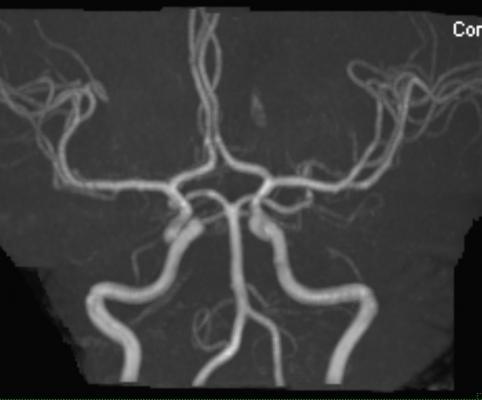

April 29, 2016 — Bayer announced that the U.S. Food and Drug Administration (FDA) has approved Gadavist (gadobutrol) injection for use with magnetic resonance angiography (MRA) to evaluate known or suspected supra-aortic or renal artery disease. The injection was approved for use in adult and pediatric patients (including term neonates).

In the studies, gadobutrol met the primary objective of superior assessability (ability to see more vessel segments) and non-inferior sensitivity and specificity as compared to non-contrast MRA. Gadobutrol-enhanced MRA demonstrated statistically significant higher assessability (visualization) versus non-contrast MRA images.

The GEMSAV (Gadavist-Enhanced MRA of the Supra-Aortic Vessels) study evaluated 457 patients with known or suspected disease of the supra-aortic arteries. Efficacy was evaluated based on visualization and performance for distinguishing between normal and abnormal anatomy. Significant stenosis was defined as at least 70 percent.

- Gadavist MRA significantly improved visualization, or assessability, (range across three readers: 88-97 percent) as compared to unenhanced MRA (range across three readers: 24-82 percent);